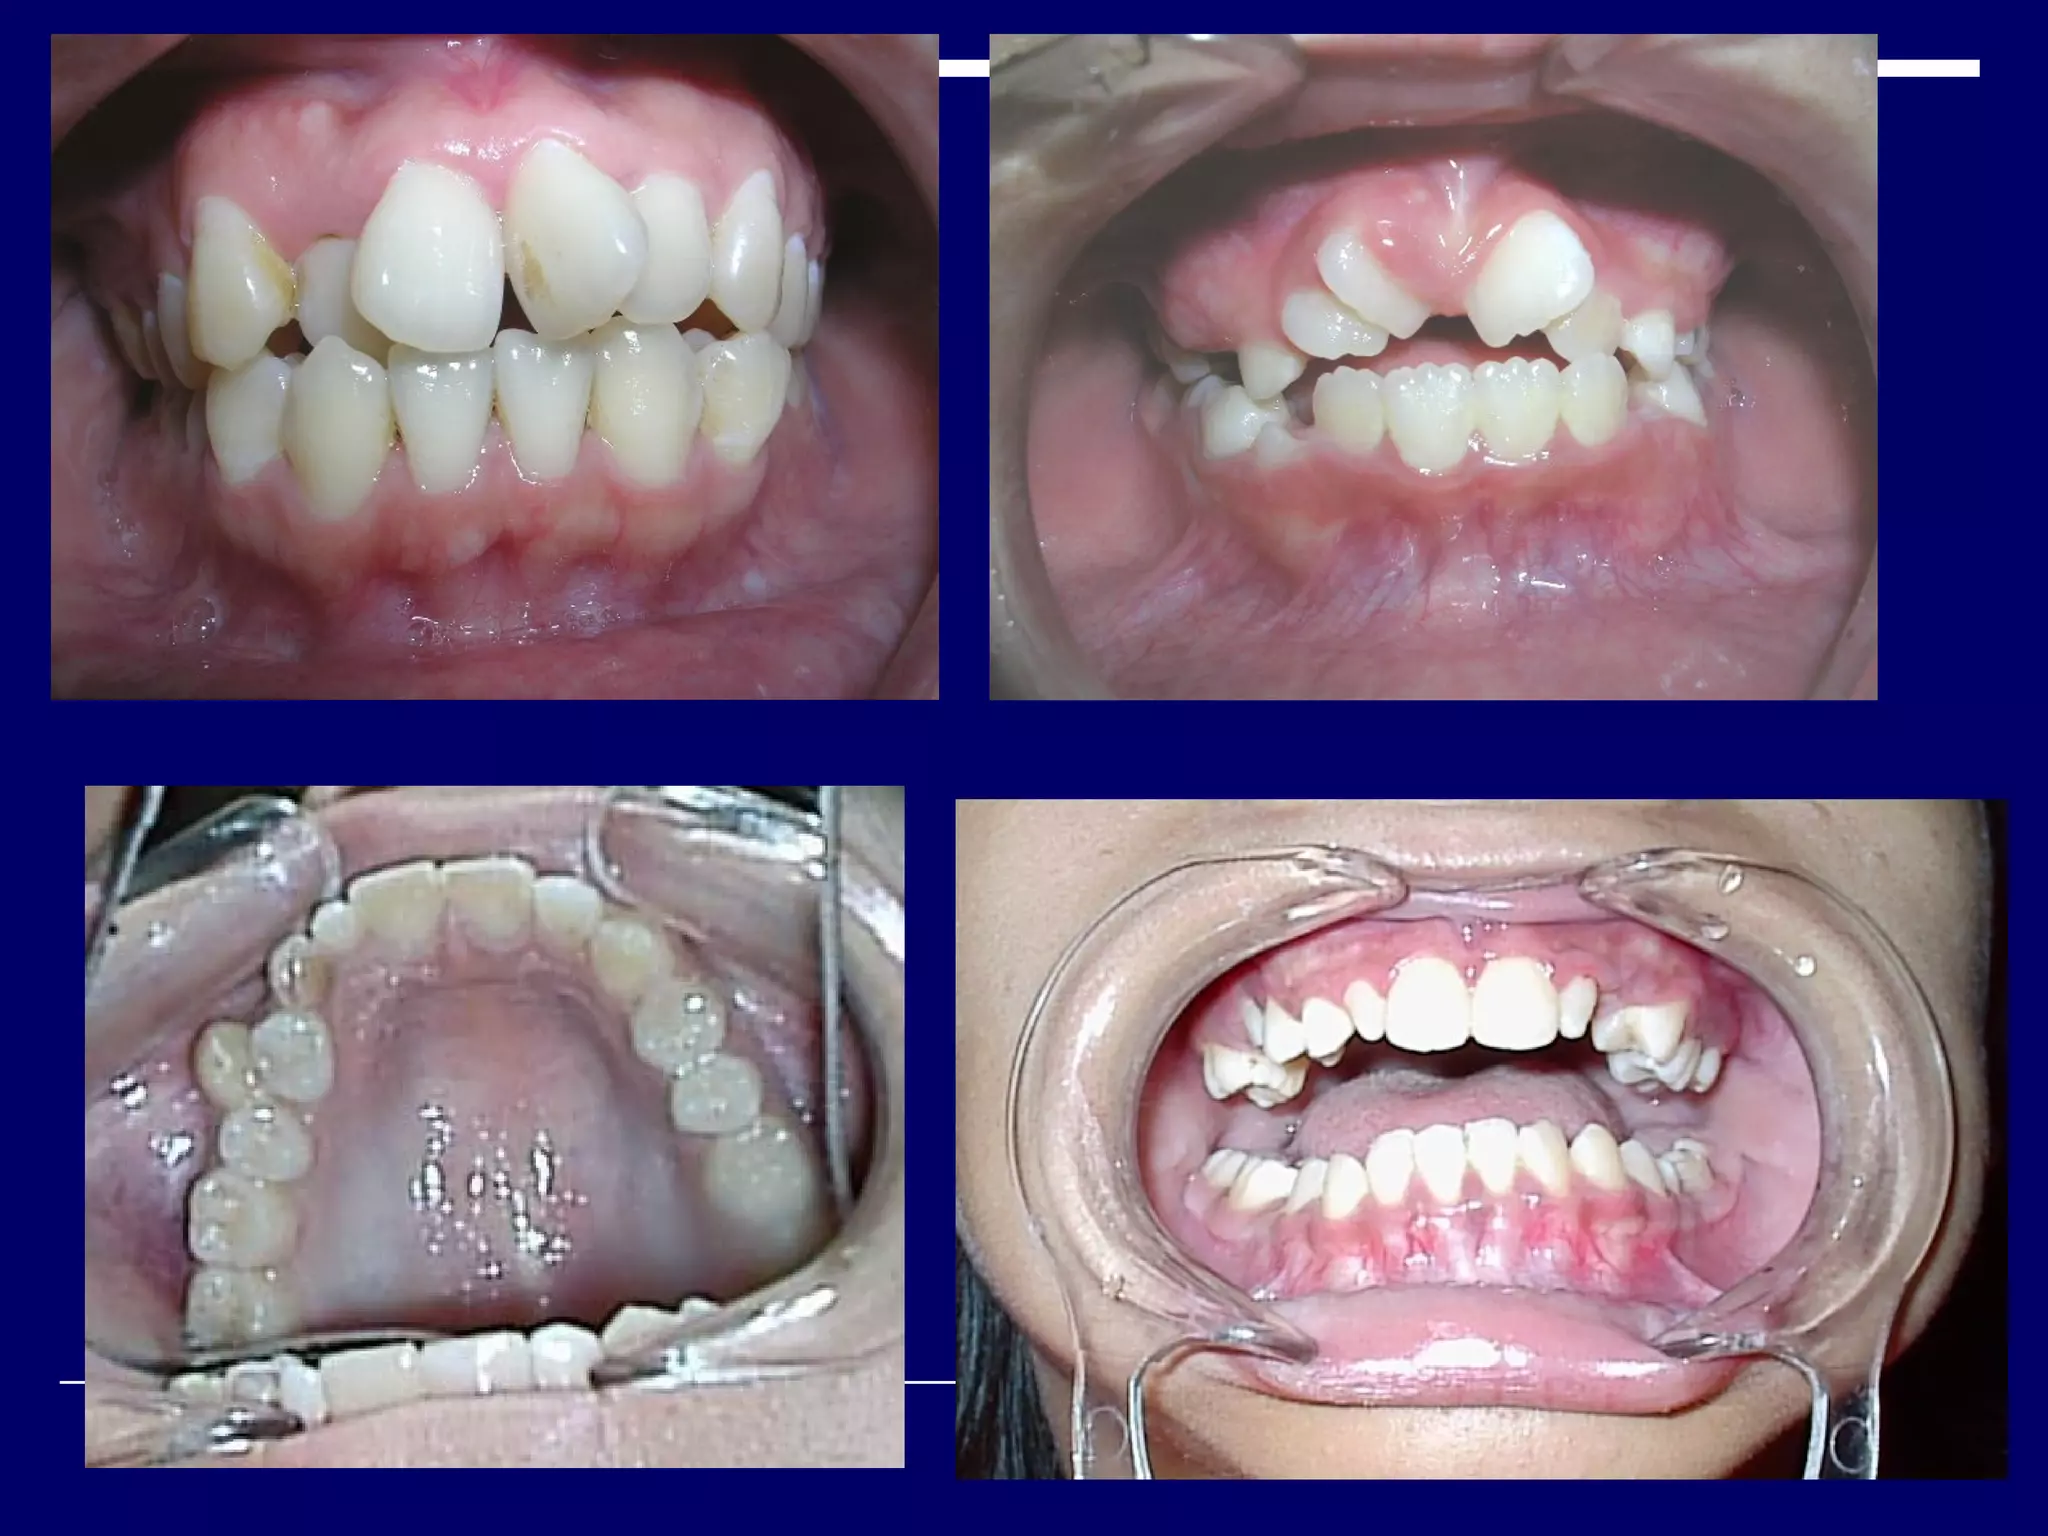

CLASS I MALOCCLUSION.

Mesiobuccal cusp of upper first permanent molar

occludes into the buccal developmental groove of the

lower first permanent molar.

Line of occlusion is incorrect.

There may be crowding, spacings, rotated teeth,

supernumerary tooth etc.

ANGLE’S CLASSIFICATION OFMALOCCLUSION. CLASS I MALOCCLUSION. Mesiobuccal cusp of upper first permanent molar occludes into the buccal developmental groove of the lower first permanent molar. Line of occlusion is incorrect. There may be crowding, spacings, rotated teeth, supernumerary tooth etc.